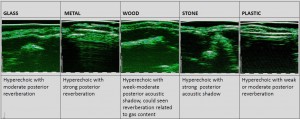

-Έγχυση Πληρωτικών Υλικών (Fillers)